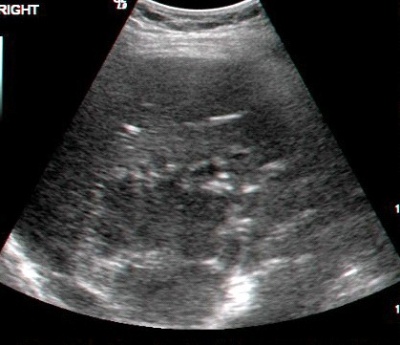

- באולטרה-סאונד ניתן להבדיל בין גוש סולידי לגוש כיסתי בכבד. מכשיר זה הינו חיוני לאבחון של מורסות הכבד (תצלום 39.10).